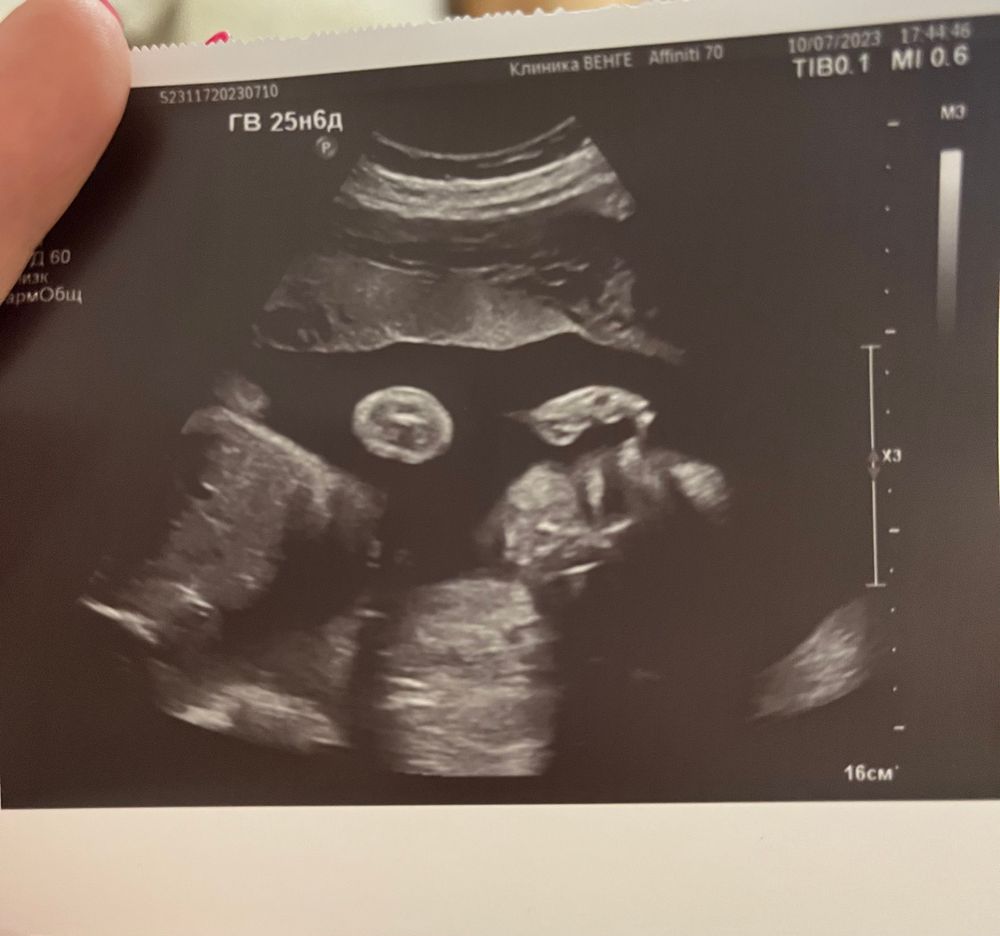

Узи в почти 26 недель))

Пошла на узи посмотреть на своего малыша, все в норме, вес уже 1кг. Но малыш проспал все узи, никак не смогли разбудить. Сделали только такое фото😂 повернулся к нам спиной, показывал попу, а это хоть как то успели запечатлить😅

В заключении написали, что соответствует уз 27-28 недель, ну мы так и так опережали на 5 дней с 1 скрининга)

Евгения, это вот в конце удалось сфоткать личико 😂😂😂 а до этого ни в какую, и то, это нам повезло прям 😅